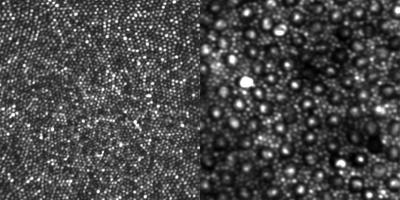

Rods are much more numerous than cones and are vastly more sensitive to light. With the optical design method successfully demonstrated by Dubra's team, even the smallest cone cells at the center of the retina, known as the foveal center, can be seen very clearly. Rods can be seen clearly in a less central retinal location. (See Fig. 1)

Though earlier AO systems could effectively image cones and have become a mainstay of high-resolution retinal imaging research, the smaller rods, which outnumber cones 20 to 1 in the retina, have eluded clear and contiguous observation in the living eye.

The breakthrough in the design of the AO instrument that led to clearly visualizing rods was, according to Dubra, "embarrassingly simple, and relied on well-known equations and concepts." By simply folding the spherical mirrors that act as lenses in the instrument into a three-dimensional structure, the image quality of the retina was improved sufficiently to clearly resolve the contiguous rod mosaic, as well as the entire cone mosaic at the foveal center.